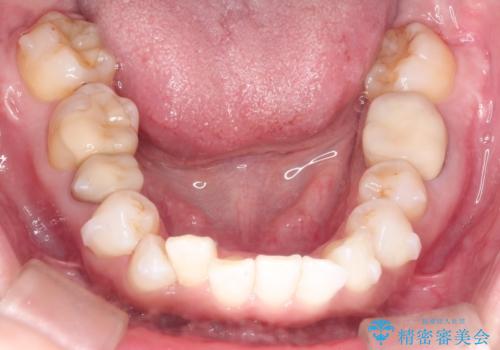

インビザラインによる非抜歯矯正 ガタガタな歯並びを整った歯並びへ

- 上下の全体的ながたつきが気になるとのことで来院されました。

全体的に歯と歯の間にわずかに隙間を作り、歯を並べました。